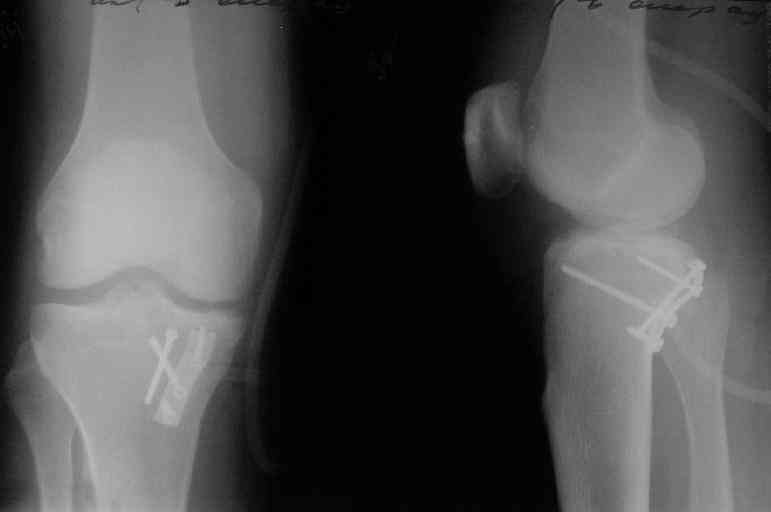

Операция из разряда травматологической "экзотики" прошла

успешно. Доступ понравился:анатомичный, хорошая визуализация, удобно

работать и оператору и ассистентам. Наложили пневможгут, но

воспользовались им только на этапе ревизии сустава. Фрагмент

развернулся на 90 град. на 2-ух "жгутах": медиально - сухожилие

m.semitendinosus, латерально - задняя крестообразная

связка. Мобилизовали,развернули и уложили на место без особого

труда. Фиксировали отмоделированной 1/3-трубчатой пластиной. Мениск

оказался неповрежден. Сустав стабилен. Обошлись без

иммобилизации, планируем начать ранние движения. Остальное на

фото, дополнительно приложены корональные срезы КТ.